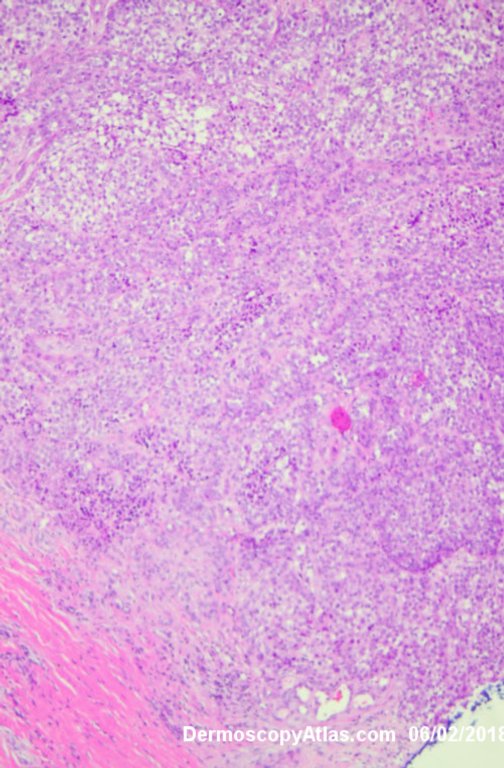

Site: Leg

Diagnosis: Melanoma invasive

Lady in her early 80s who presented with this lesion on her ankle. The pigmented area had been there for some time but the pink area was bleeding and new. Shave of surrounding area and a punch biopsy of the new pink area showed mainly surrounding in situ melanoma with invasive melanoma in the pink area 1.8 mm thick. Having a 2cms margin excision of the whole area and a graft.